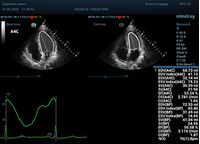

Что могут предложить современные приборы? Приборы нашего времени являются мощными вычислительными машинами, способными обрабатывать полученную информацию даже без помощи человека. Система автоматического вычисления фракции выброса – AUTO EF на приборах серии Resona компании Mindray сделает все за вас. За пару секунд прибор сам отыщет нужную фазу сердечного цикла и произведёт измерение и расчеты, а также покажет график изменения объема в сердечном цикле. От Вас требуется только получить качественное 4С и 2С сечение. Впрочем, прибор всегда оставляет возможность коррекции, если доктор имеет свое мнение на расположение точек планиметрии или момента измерения по ЭКГ каналу.